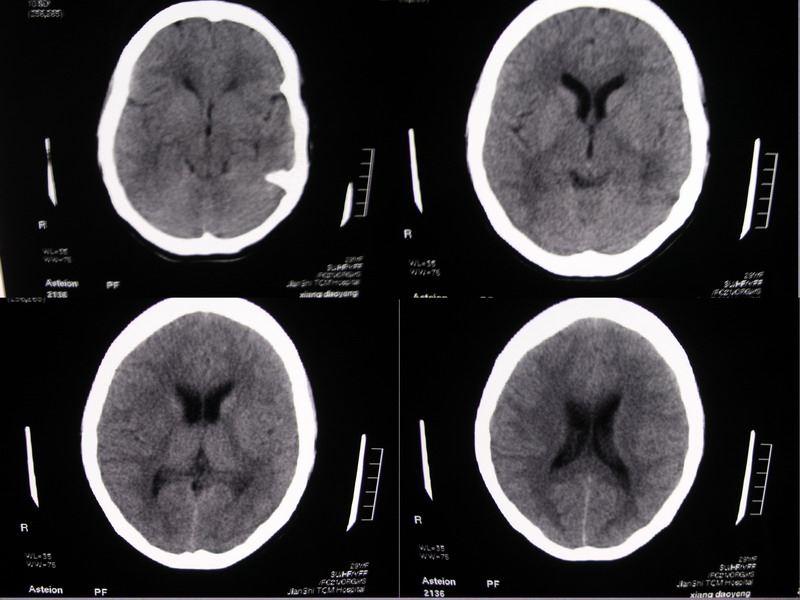

向××,女,29岁,二十天前高热,抗炎治疗后双眼斜视,肌无力,双下肢张力ii级。

除侧脑室额角轻度扩大外,余未见异常。

侧脑室稍扩大,余未见确切异常强化征,请结合脑脊液及脑脊髓mri检查

侧脑室稍扩大,余未见明显异常强化征。

双侧脑室有轻度扩大,增强看脑沟裂显示还是模糊的.时间较长应该考虑脑膜炎.